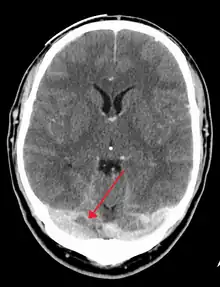

There are various neuroimaging investigations that may detect cerebral sinus thrombosis. Cerebral edema and venous infarction may be apparent on any modality, but for the detection of the thrombus itself, the most commonly used tests are computed tomography (CT) and magnetic resonance imaging (MRI), both using various types of radiocontrast to perform a venogram and visualise the veins around the brain.[4]

Magnetic resonance venography employs the same principles, but uses MRI as a scanning modality. MRI has the advantage of being better at detecting damage to the brain itself as a result of the increased pressure on the obstructed veins, but it is not readily available in many hospitals and the interpretation may be difficult.[11]